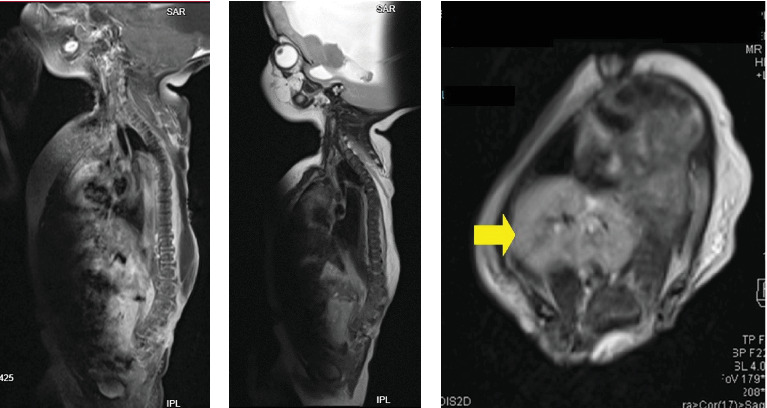

Meningomyelocele and meningocele are types of neural tube defects, which are congenital abnormalities of the spine and spinal cord. These conditions are frequently encountered by pediatric neurosurgeons worldwide and represent a significant public health concern due to their association with a range of collateral conditions, other malformations, and increased morbidity. While many cases can be identified during prenatal ultrasound screenings, this is often challenging in resource-limited settings with poor health-seeking behaviors. Surgical intervention is the primary treatment for these defects, and while various methods are described in the literature, larger defects require complex flaps and techniques, with limited options available. Beyond early surgical intervention, patients require lifelong care involving multidisciplinary medical teams.

Abstract Image